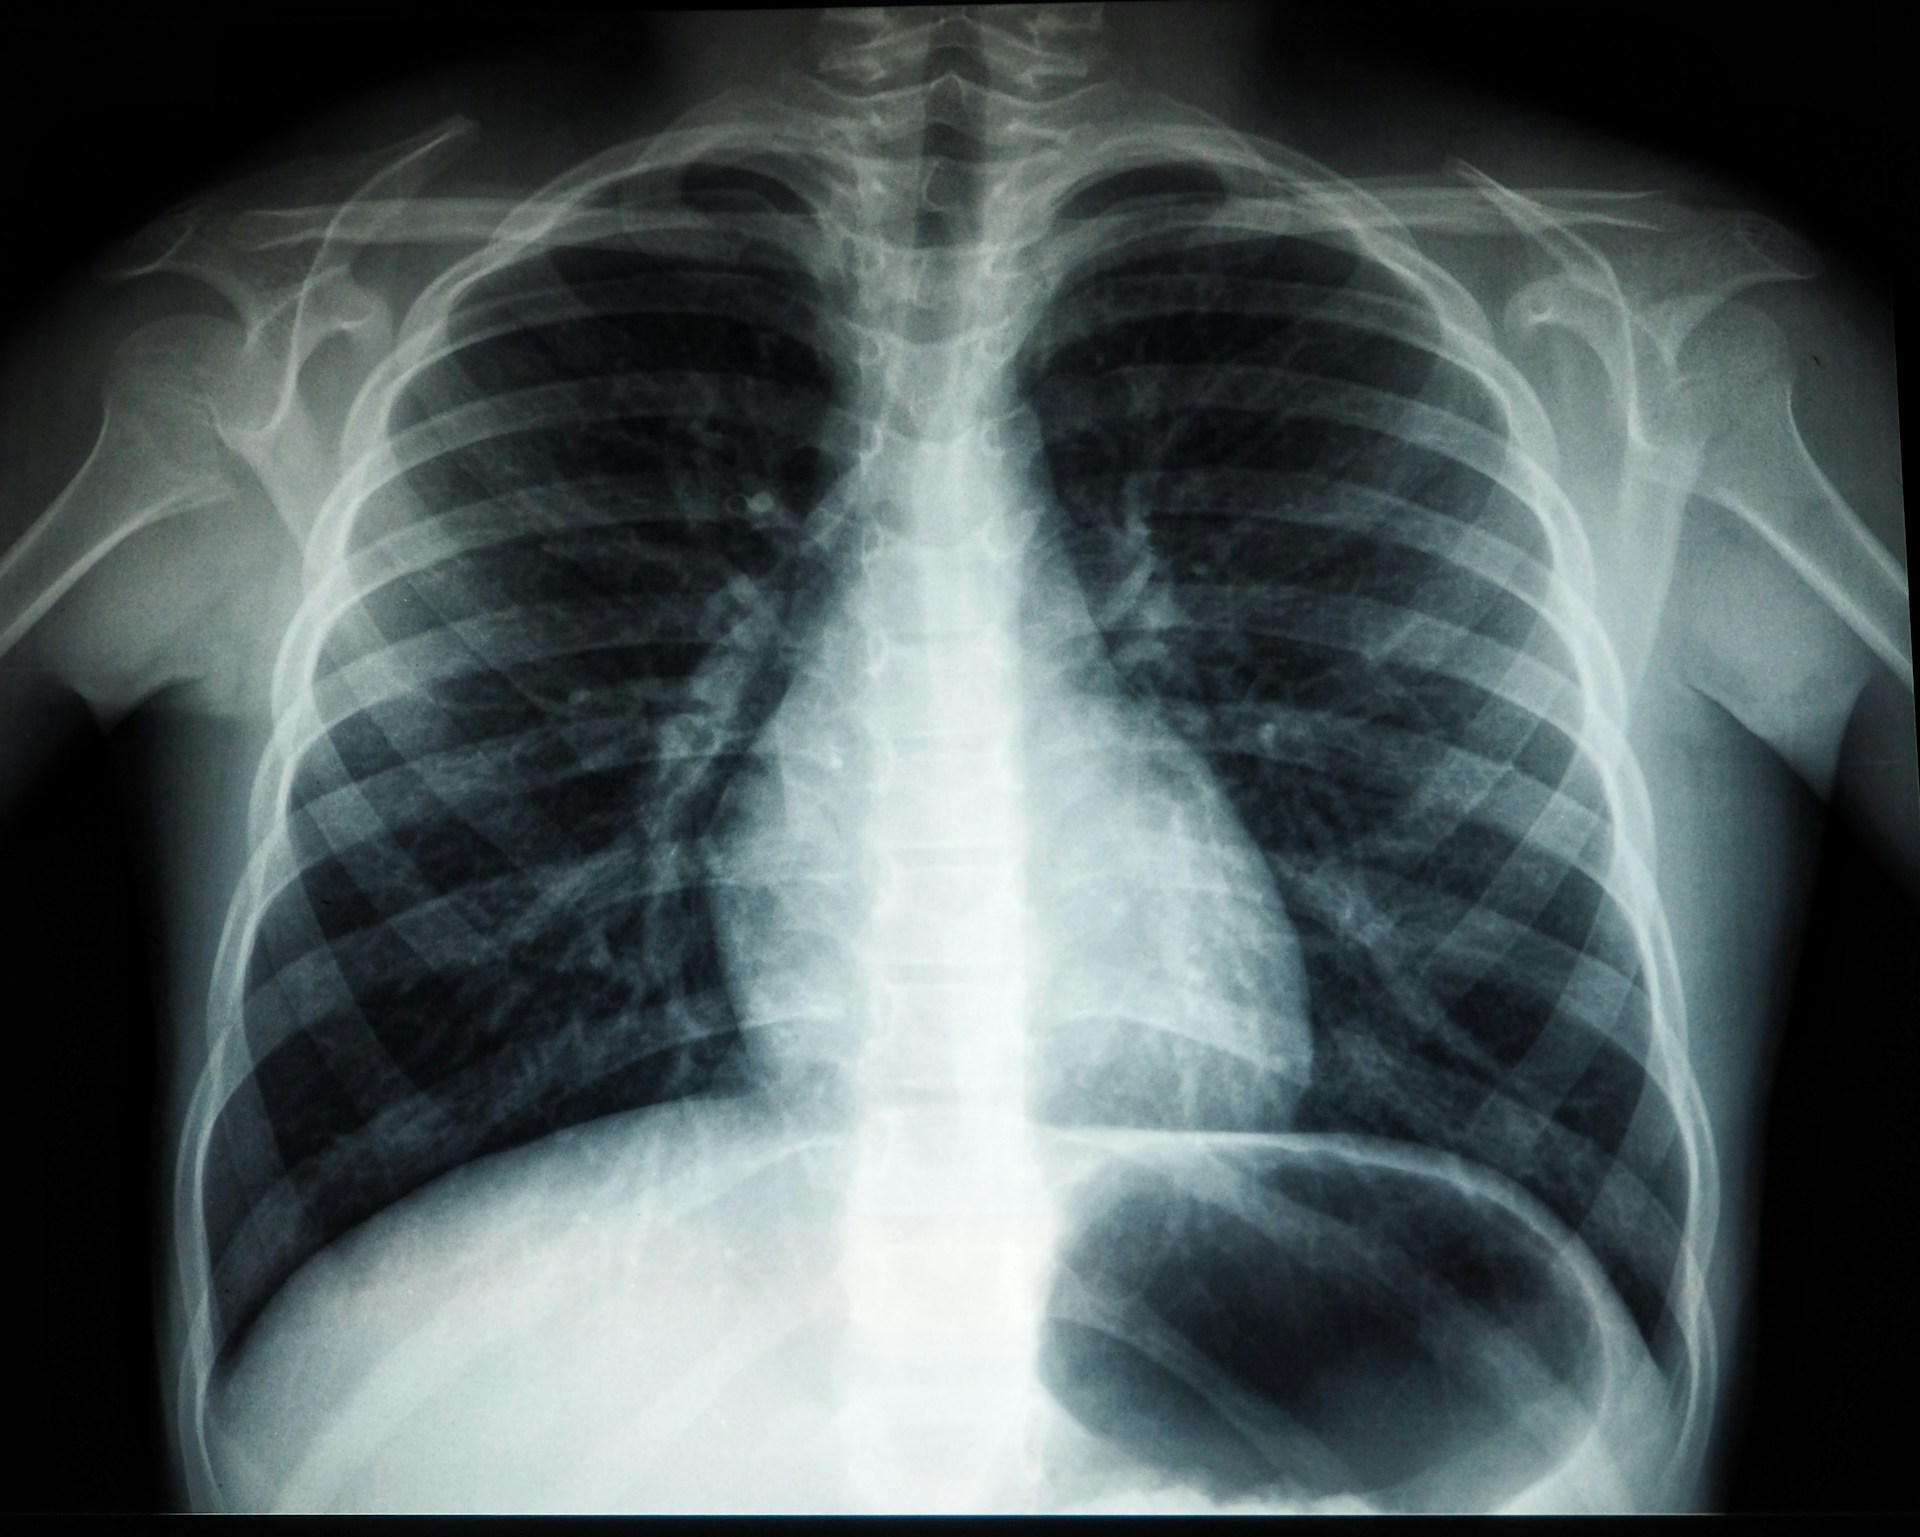

X-Rays

In 1895, Wilhelm Röntgen noticed a strange glow from a coated screen while he experimented with cathode rays behind a shield. Invisible rays were slipping through cardboard and cloth, painting bones and rings on plates. He called them X-rays, the unknown kind. Within months, surgeons could see fractures before cutting, and engineers could inspect metal without prying it apart. A lab accident widened human sight, trading guesswork for images and changing medicine and industry in a single stroke.